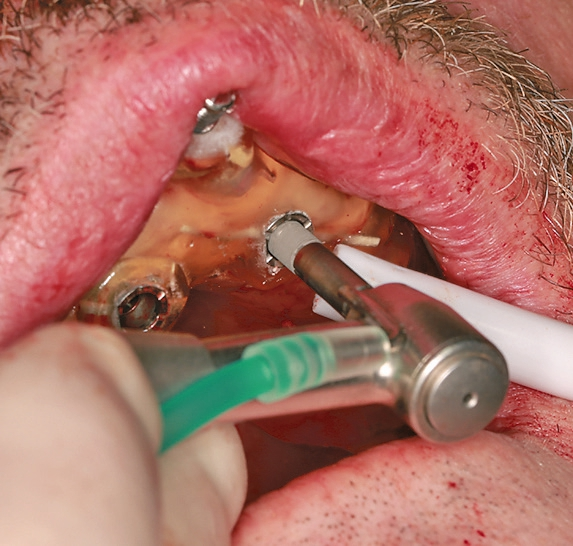

Mit dem Bohrerset (Abb. 20) wird implantiert. Nachdem die Bohrschablone fixiert wurde (Abb. 9) müssen nun gemäß Bohrprotokoll die Implantate vorgebohrt und danach inseriert werden. Abbildung 10 zeigt, dass die Bohrer aus dem Set sowohl die Größe richtig aufbereiten, wie auch die Tiefe berücksichtigen, d.h. bei exaktem Sitz der Schablone kann ganz präzise implantiert werden. Dies betrifft auch das Einbringen der Implantate; auch diese werden navigiert eingebracht (Abb. 11).

In Abbildung 12 ist die Einbringhilfe schön zu sehen. In Abbildung 13 kann man die relativ geringe Höhe der Schablone erkennen. Dadurch ist ein Implantieren auch im hinteren Bereich möglich. Gerne werden die Schablonen zu dick oder zu hoch gefertigt, so dass man schon ab dem 6er Bereich den Bohrer nicht mehr in die Schablone bekommt. Dann ist der Aufwand sehr groß, um damit zu implantieren. Aber hier ist dies erfreulicherweise möglich, da durch das C-Guide Konzept, eine ausreichende Führung der Bohrer gewährleistet ist. Trotz den niedrigen Hülsen ist eine Bohrführung gegeben! Nachdem nun alle Implantate eingebracht wurden, zeigt die klinische Kontrolle (Abb. 17) und auch das Abschlussbild im OPG (Abb. 18), dass die Implantate genau nach Planung gesetzt wurden (Abb. 19).